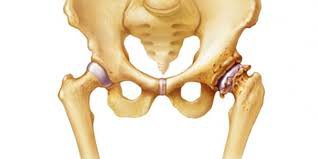

Hoại tử xương

Trong bệnh hoại tử xương, máu sẽ không cung cấp đủ máu tới các mô xương và gây hoại tử. Bệnh này chủ yếu ảnh hưởng đến đầu xương đùi. Xương vai, đầu gối, cổ tay hoặc mắt cá chân cũng có thể bị ảnh hưởng. Đa số các trường hợp có nguyên nhân là do chấn thương tại xương, ví dụ như gãy xương hông.

Người bị hoại tử xương thường sẽ phát triển tình trạng đau xương một cách từ từ. Với các tổn thương nhỏ, tình trạng hoại tử có thể tự khỏi mà không cần điều trị. Nhưng với những tổn thương xương lớn hơn, điều trị bao gồm dùng thuốc, vật lý trị liệu và/hoặc phẫu thuật.